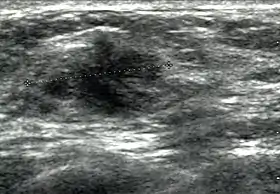

![]() Cancer ultrasound image | |

Breast ultrasound is a medical imaging technique that uses medical ultrasonography to perform imaging of the breast. It can be performed for either diagnostic or screening purposes[1] and can be used with or without a mammogram.[2] In particular, breast ultrasound may be useful for younger women who have denser fibrous breast tissue that may make mammograms more challenging to interpret.[3][4]

Elastography is a type of ultrasound examination that measures tissue stiffness and can be used to detect tumours.[7] Breast ultrasound is also used to perform fine-needle aspiration biopsy and ultrasound-guided fine-needle aspiration of breast abscesses.[8]